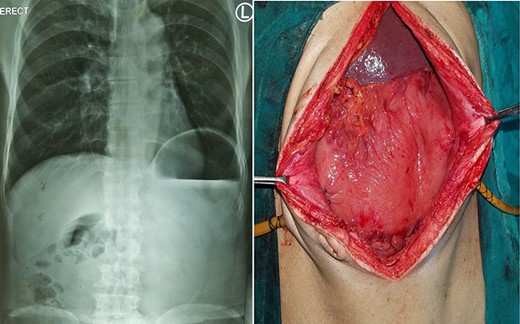

Chronic gastric volvulus, showing raised left hemi-diaphragm in chest X-ray, with intraoperative placement of double gastrostomy tube for fixation.

A 75-year-old male presented to the emergency with severe pain in the epigastrium, multiple episodes of non-bilious vomiting and epigastric fullness for the past 2 days. There was no history of weight loss, anorexia, hematemesis or early satiety. Eight months before, he had similar complain (resolved spontaneously), was admitted, and evaluated with upper GI endoscopy and CT abdomen, with normal findings. On examination, patient was tachycardic but normal blood pressure. There was epigastric fullness with mild tenderness. Blood investigations revealed normal hemoglobin, but leukocytosis (16 000 cells/mm3). The renal function test and serum chemistry were normal. Chest X-ray was done, which showed elevated left hemi-diaphragm with large gastric shadow beneath it (Fig. 3). In view of recurring symptoms, chronic gastric volvulus was considered as differentials. On further imaging with CT abdomen, it confirmed gastric volvulus. Patient was taken up for emergency laparotomy. Intraoperatively, organo-axial gastric volvulus secondary to diaphragmatic eventration was seen. It was de-rotated and fixation of the stomach was performed by double, non-draining tube gastrostomy (at two points, body and antrum) with sham gastrojejunostomy to prevent recurrence (Fig. 3). No attempt at the plication of eventration was done due to the technical difficulty, splenic capsular tear and secured stomach fixation. The patient did well postoperatively and was discharged on Day 8. At 38 months follow-up, the patient is asymptomatic.